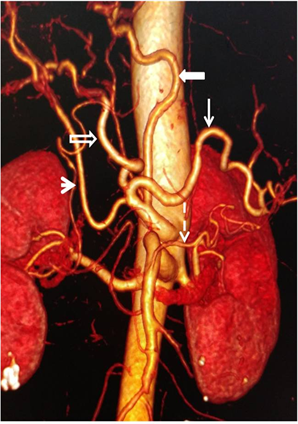

One hundred and twenty-eight patients (80%) had a classical anatomical configuration of celiac trunk, while thirty-two (20%) had at least one AV. Two AVs were found in 15 patients (9.4%) while five other patients (3.1%) had more than two AVs. Bifurcation of celiac trunk was the most common type of AV with a total of 14 patients, including hepato-splenic bifurcation (Figure 2), with 12 patients (7.5%). The second type of bifurcation found was gastro-splenic with 1.3% (Figure 3). Collateral arteries were the second most frequent type of AVs with a

Figure 2. Enhanced abdominal CT-scan showing on 3D reconstruction, a hepato-splenic bifurcation with a common hepatic artery (hollow arrow), a splenic artery (full arrow) and a stomachic coronary artery of inferior mesenteric artery origin (thin arrow).

Figure 3. Enhanced abdominal CT-scan showing on 3D reconstruction, a gastro-splenic bifurcation with a stomachic coronary artery (hollow arrow), a splenic artery (full arrow) and a common hepatic artery (arrow head).